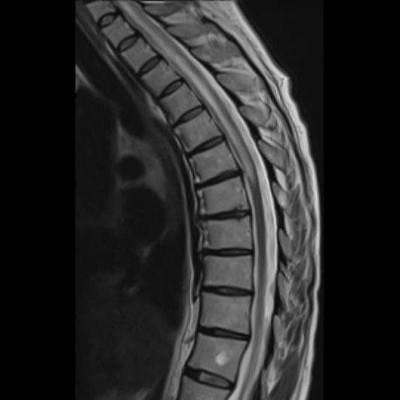

- (A) Torakal MRG’de sagital görüntülerde üst-orta torakal düzeyde T2A hiperintens (oklar), T1A izo-hipointens (ok) uzun segment ekspansil sinyal değişikliği izlenmekte olup sagital postkontrast T1A’da kontrast tutulumu mevcuttur (oklar). Bulgular longitudinal ekstensif transvers miyelit (LETM) ile uyumludur.

- Transvers miyelit sıklıkla santral gri cevheri etkileyen ve üç veya daha fazla vertebral gövde uzunluğunu etkilemektedir (LETM).

- Transvers kesitlerde, santral kordu tutma eğilimindedir.

- Omurilik atrofisi ve ekspansiyon/ödem MS’e göre daha fazla görülür.

- Kontrast madde enjeksiyonu sonrasında neredeyse tüm akut NMO lezyonları, yamalı, düzensiz veya periferik olarak kontrastlanma gösterir.